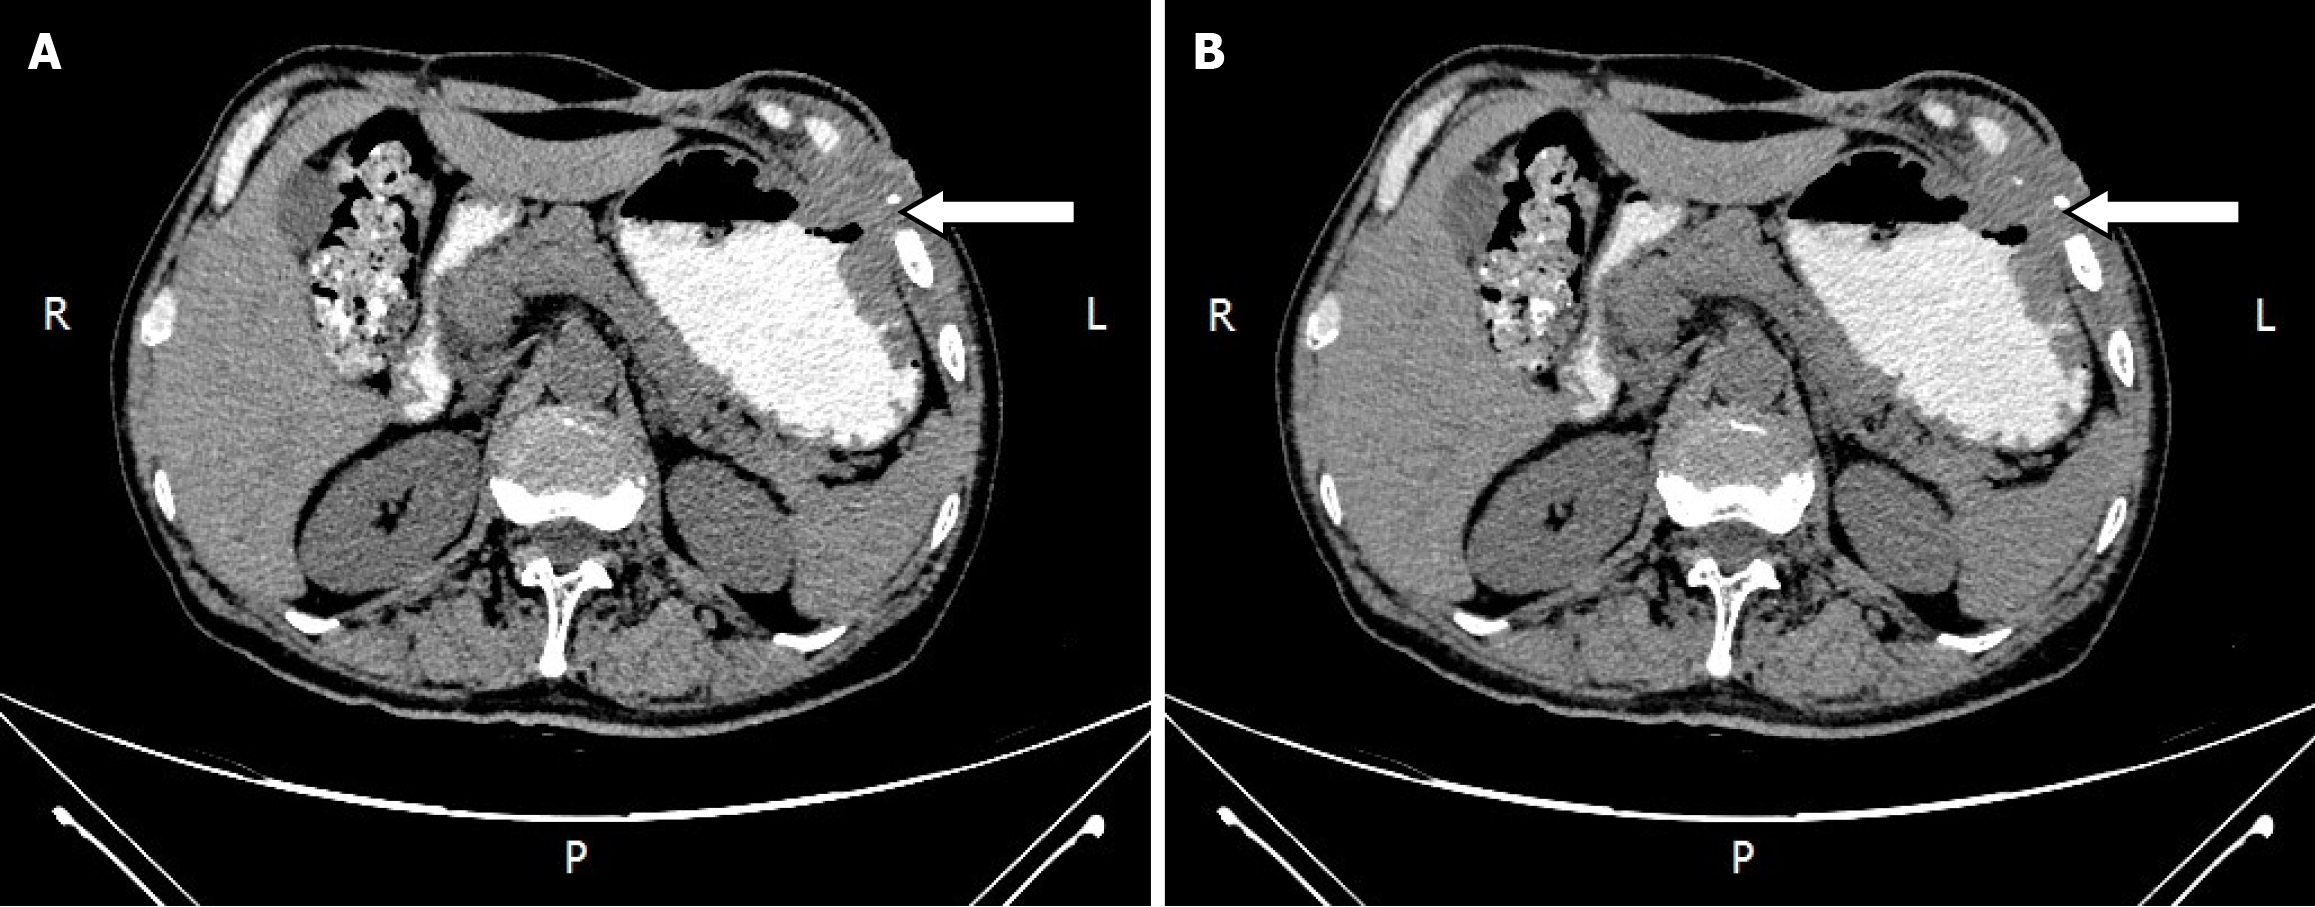

An abdominal computed tomography (CT) scan showed diffuse edema with pneumatosis of the antero-inferior chest wall and abdominal wall, and cellulitis was considered (Figure 1).